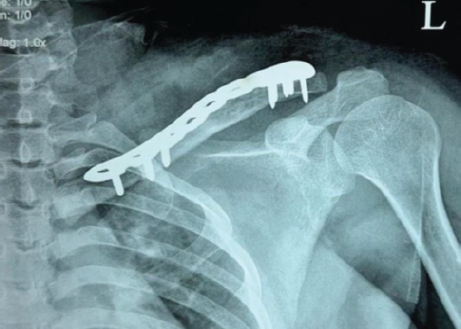

Considering the young age of the patient, the aim of our treatment plan was to salvage the clavicle and preserve the acromioclavicular joint function – which was achieved through extended mechanical and chemical curettage with high speed burr and hydrogen peroxide respectively, cancellous autograft placement from iliac crest, and augmentation plating (Figs. 4, 5, 6, 7).

Figure 7: X-ray left shoulder anteroposterior view – immediate post-operative.